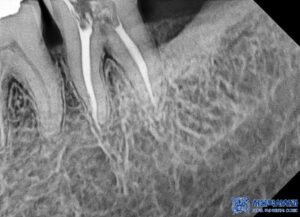

더 정밀히 확인하기 위해,

엑스레이 사진을

찍어보았습니다.

왼쪽 위는 치아가 없을 뿐 아니라

골흡수가 심하게 진행되어

상악동과의 거리가 가까워져

뼈가 부족한 상황이었습니다.

또한 오른쪽 위 어금니들 역시

치아를 지탱하는 잇몸뼈가

많이 흡수되어 있는 것이

확인되었습니다.

임플란트 식립을 위해서는

3D CT 사진을 촬영하여

더 자세히 보아야 하는데요.

평면적인 사진과 같이

뼈가 많이 녹아있는 것을

볼 수 있습니다.